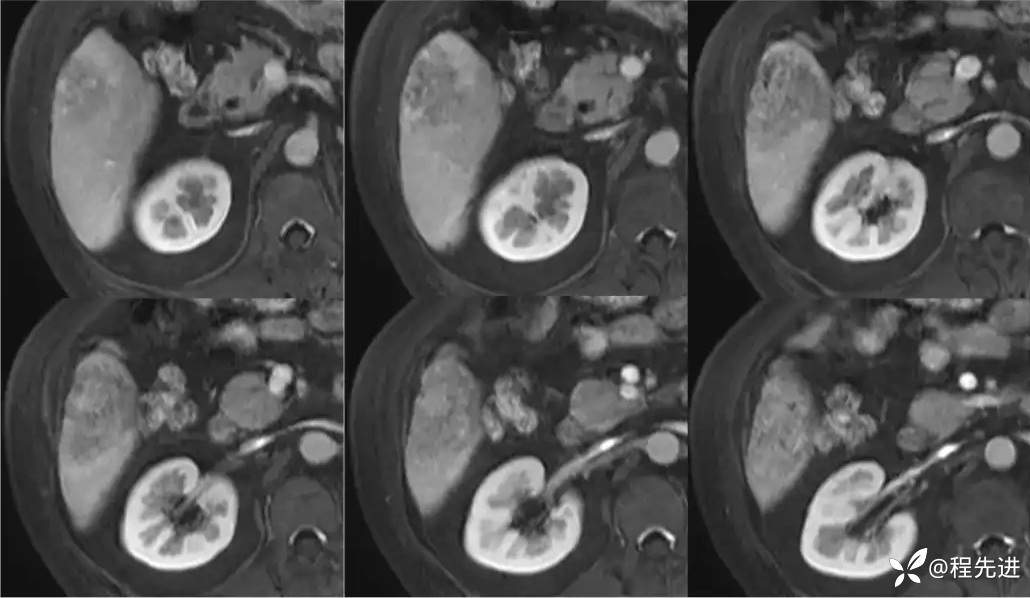

T1同反相位:

T2:

DWI、ADC

T1蒙片:

动脉期: